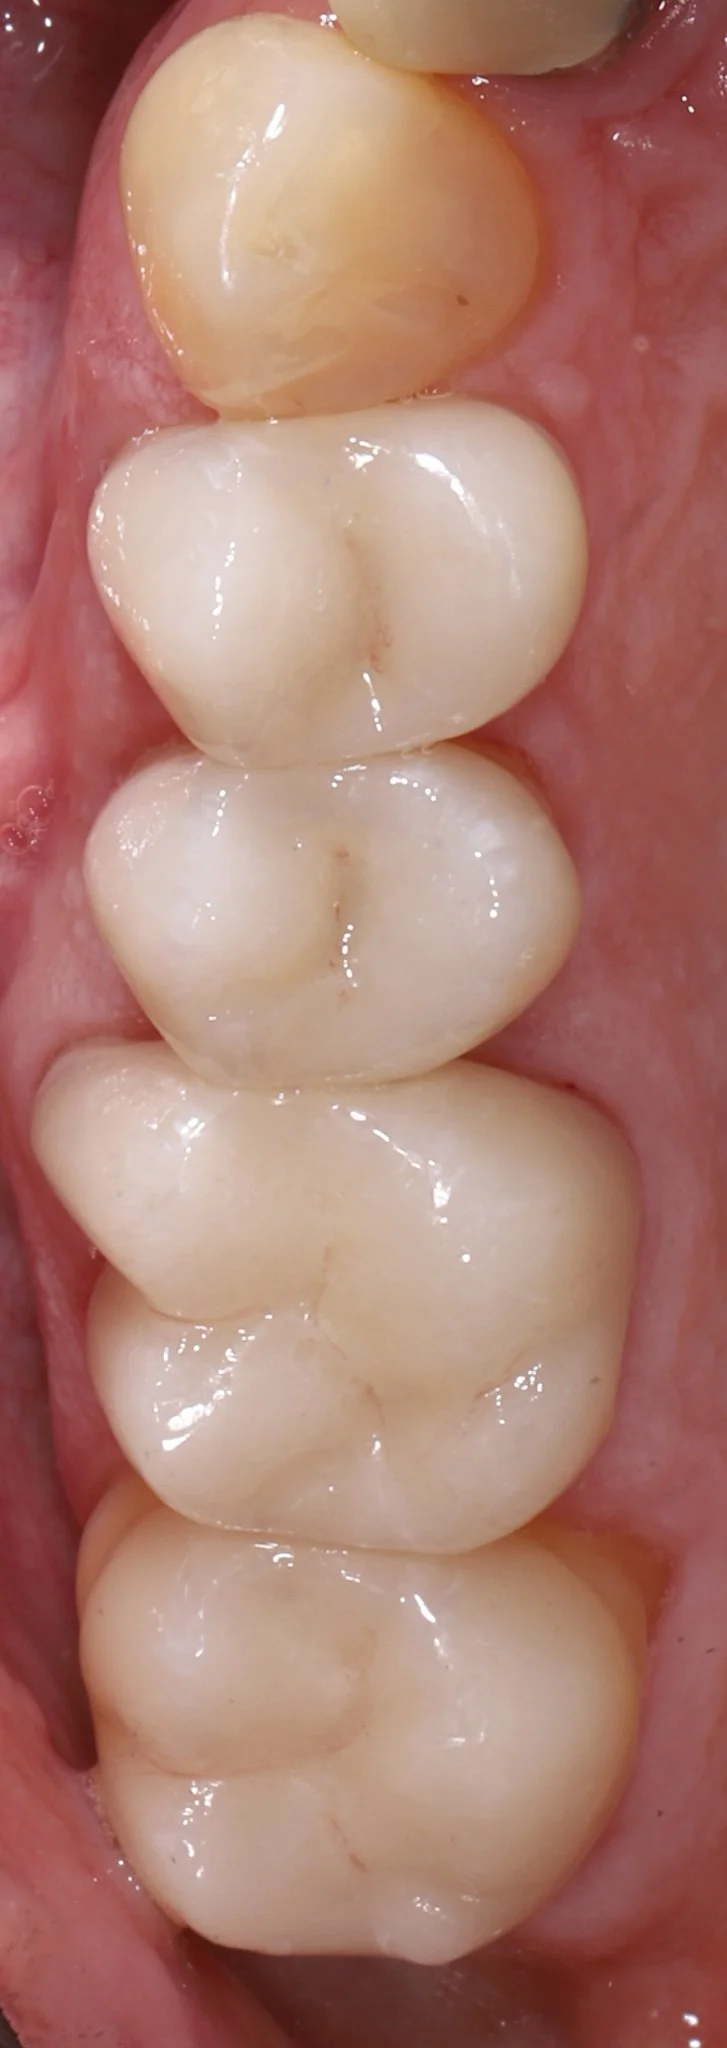

Close-up of four white molar teeth inside a person's mouth.

After: Proper fit, gum tissue health, natural restorations